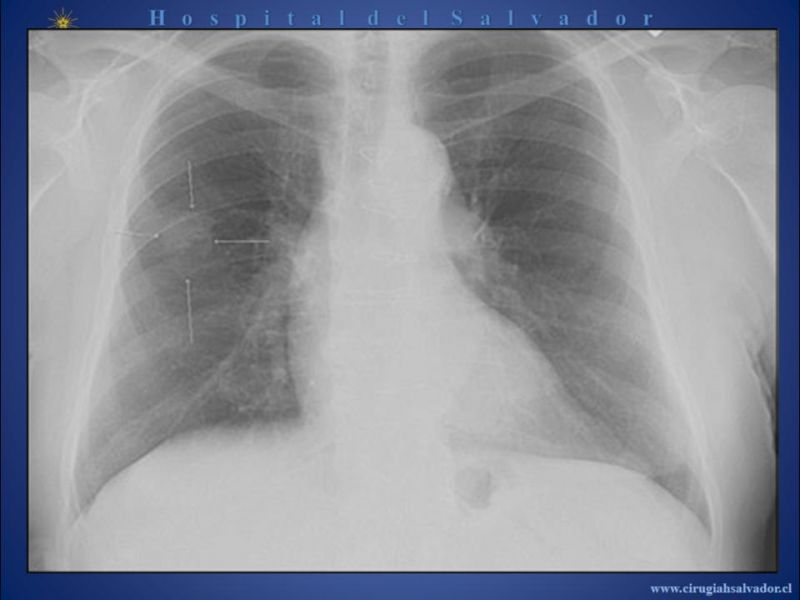

Nódulo Pulmonar Solitario

Cirugía Torácica

| Autor: Dr. Rodrigo Subiabre Ferrer